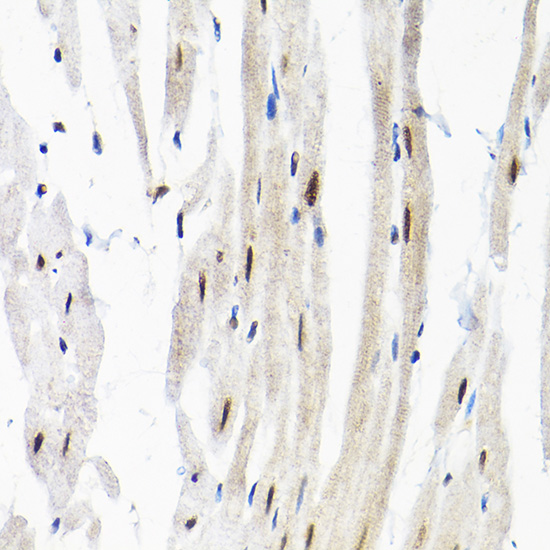

Immunohistochemistry of paraffin-embedded rat heart using SNRPF Rabbit pAb.